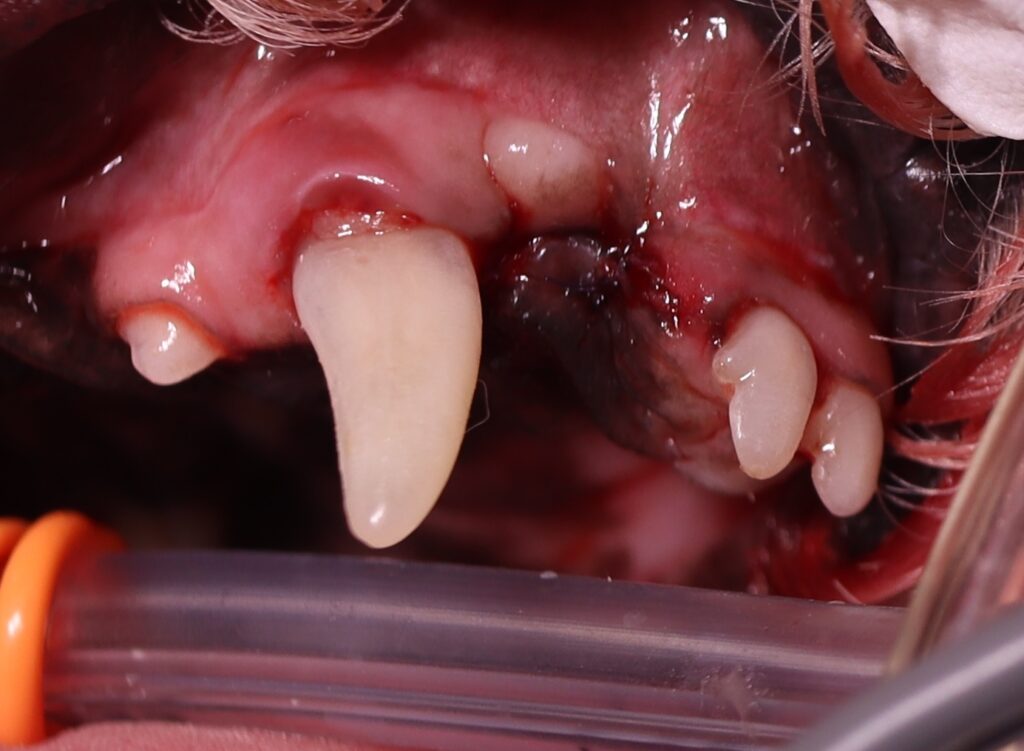

このトイプードルちゃんは「歯石が気になる」とのことで来院されました。

- 上顎切歯の密生(叢生)

- 犬歯との間の歯石沈着

- 歯科レントゲン検査で重度の歯槽骨融解を確認

- 右上顎の第3切歯を抜歯

- 骨欠損部には**PRF(自己血由来の再生材料)を充填